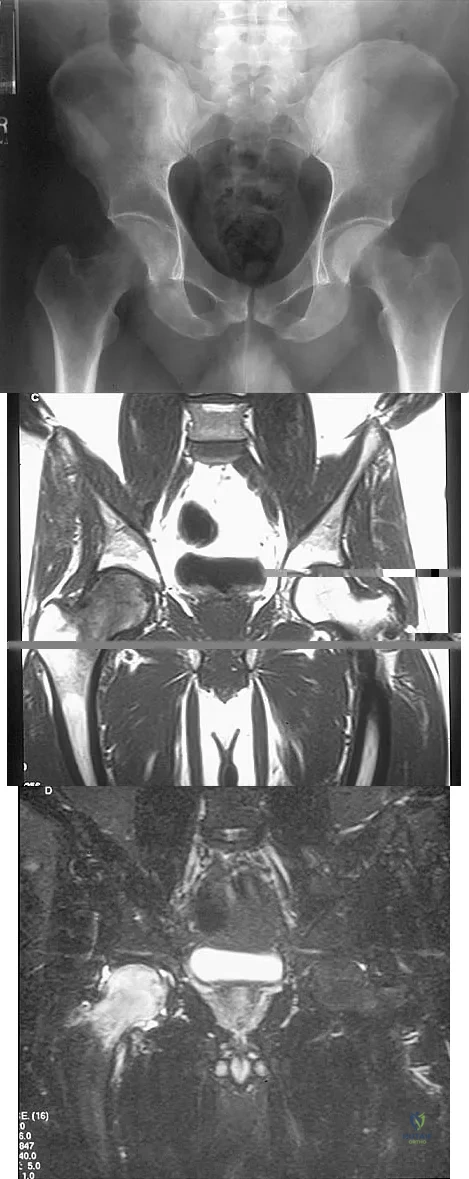

A 13-year-old girl has had increasing left hip pain for the past 4 months. A radiograph, bone scan, MRI scan, and photomicrograph are shown in Figures 1a through 1d. Which of the following immunohistochemistry results would confirm the most likely diagnosis?

Explanation